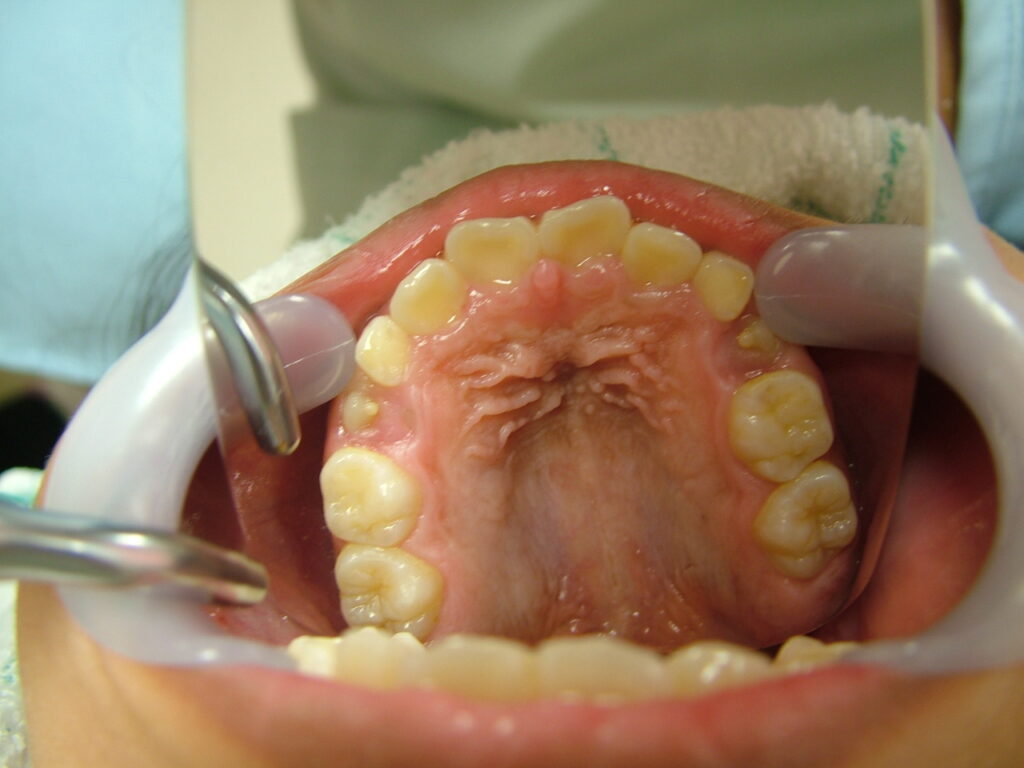

治療前

• 診断:1級過蓋咬合、上下前歯叢生、上顎左右側切歯クロスバイト

• 治療方針:非抜歯で行う。虫歯予防(フッ素)、歯磨き指導、上下拡大床→最小限のデイスキング→マウスピース矯正→下親知らずの抜歯、保定→メンテナンス

虫歯や歯肉炎の発症なく、まずまずの状態で1期治療を終了したと思います。もう少し上下顎拡大も考えましたが口が大きくなることを考慮して、最小限のディスキングで対応しました。親御さん、子供さん共に非抜歯での矯正を希望されましたが、今後シャープな口元を希望される場合、矯正の専門医で小臼歯4本抜歯ワイヤー矯正されるのも良いかもしれません。しかし舌房が狭くなり、噛みしめが誘発された方(歯周病の悪化、肩こり、知覚過敏、不定愁訴等)を数多く見てきているため、私は成人抜歯矯正(2期治療)をやるつもりはありません。(注、私は全ての抜歯矯正を否定しているわけではありません。正しく舌房の確保、舌のポジション、上下7番のコントロールを考えた矯正医が行うのは素晴らしいと思っています。)